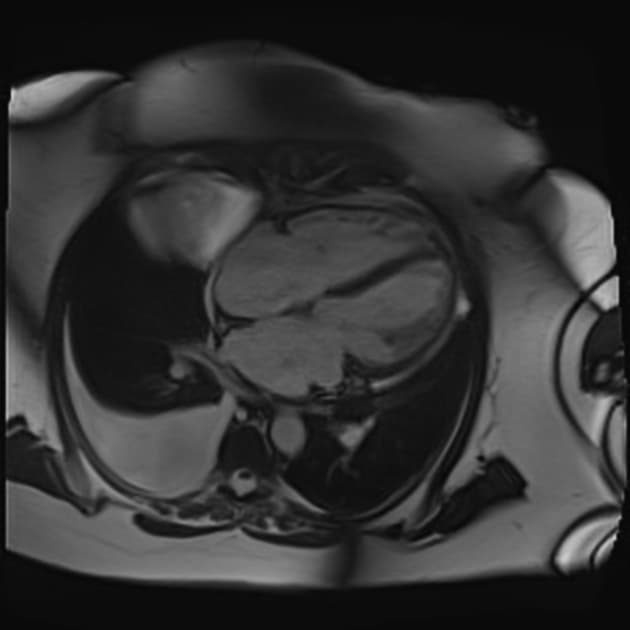

2ch cine SSFP

- Phù cơ tim (myocardial edema) vùng thấy ở thành bên từ vùng trước bên đến vùng dưới, từ đáy đến đỉnh tim.

- Tăng quang muộn gadolinium (late gadolinium enhancement - LGE) dạng mảng, dưới ngoại tâm mạc thấy ở các đoạn bên và dưới từ đáy đến đỉnh.

- Phù cơ tim khu trú (focal myocardial edema) thấy ở các đoạn bên và dưới từ đáy đến đỉnh (mũi tên xanh).

- Giá trị T1 tự nhiên tăng ở các đoạn bên đáy, giữa thất, đỉnh và các đoạn dưới được đo và thể hiện trên bản đồ màu với T1 >1150 ms (z-score >5 theo dữ liệu địa phương).

- Giá trị T2 tăng ở thành bên và dưới ở các mức đáy, giữa thất và đỉnh là bằng chứng thêm về phù cơ tim ở các đoạn này.

Tăng quang muộn gadolinium (Late gadolinium enhancement - LGE)

- Tăng quang muộn gadolinium dạng mảng trong cơ tim và khu trú dưới ngoại tâm mạc thấy trên hình ảnh IR-GE (mũi tên đỏ), là dấu hiệu đặc trưng của viêm cơ tim, phản ánh tổn thương cơ tim hoặc hoại tử cơ tim (myocardial necrosis), nhưng độ nhạy và độ đặc hiệu không cao nếu chỉ dùng riêng tiêu chí này 2.